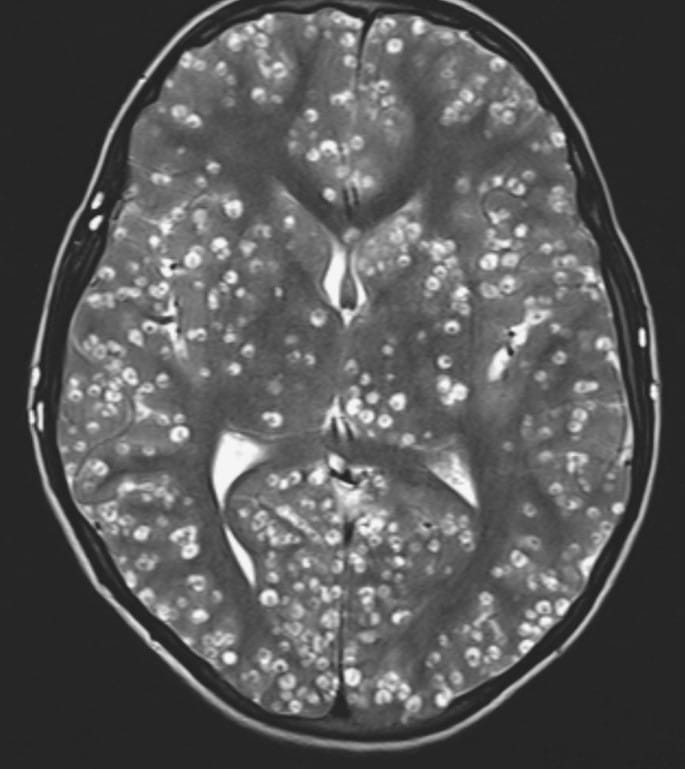

Reason for Elizabeth May’s Erratic Behaviour Finally Revealed: “Brain Bugs,” Eh?

Sidhu Singh Nov 14, 2024

Sidney, BC — Mystery solved, folks. According to a leaked hospital report, Green Party MP…